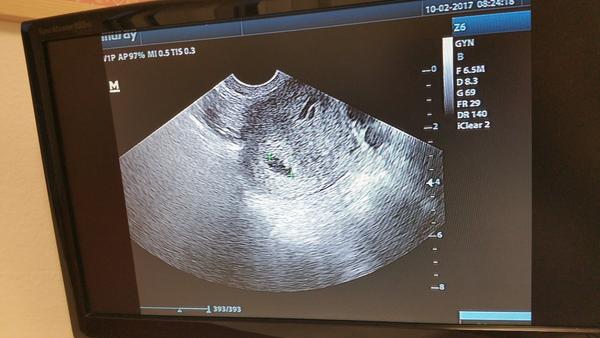

@maja129 som v 5tt. Duphaston som si dala teraz rano 1 tab. este neviem ako sa budem po nom citit 🙂 dufam ze nam pomoze a babenko donosime az do stastneho konca. A ako si sa citila pred tym nez si zacala brat duphaston?